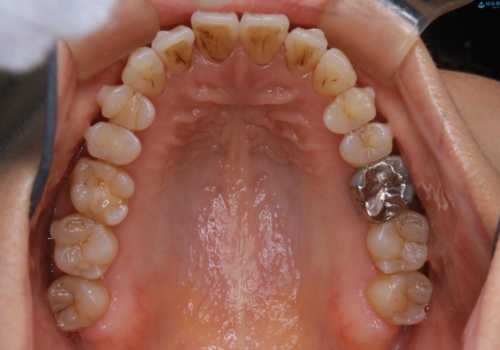

- 歯ぐきと骨が薄く、他院にて大きな矯正治療を断られた患者様です。

ワイヤー治療で行う場合、抜歯治療が第一選択となりますが、

骨と歯茎の状態を考慮した場合、抜歯をして大きく動かすことは避けたいと考えました。

そこで、インビザライン矯正で非抜歯で行うことを提案させて頂きました。

インビザライン矯正の利点の一つとして、必要最小限の動きで目的の歯並びを達成できるということがあります。